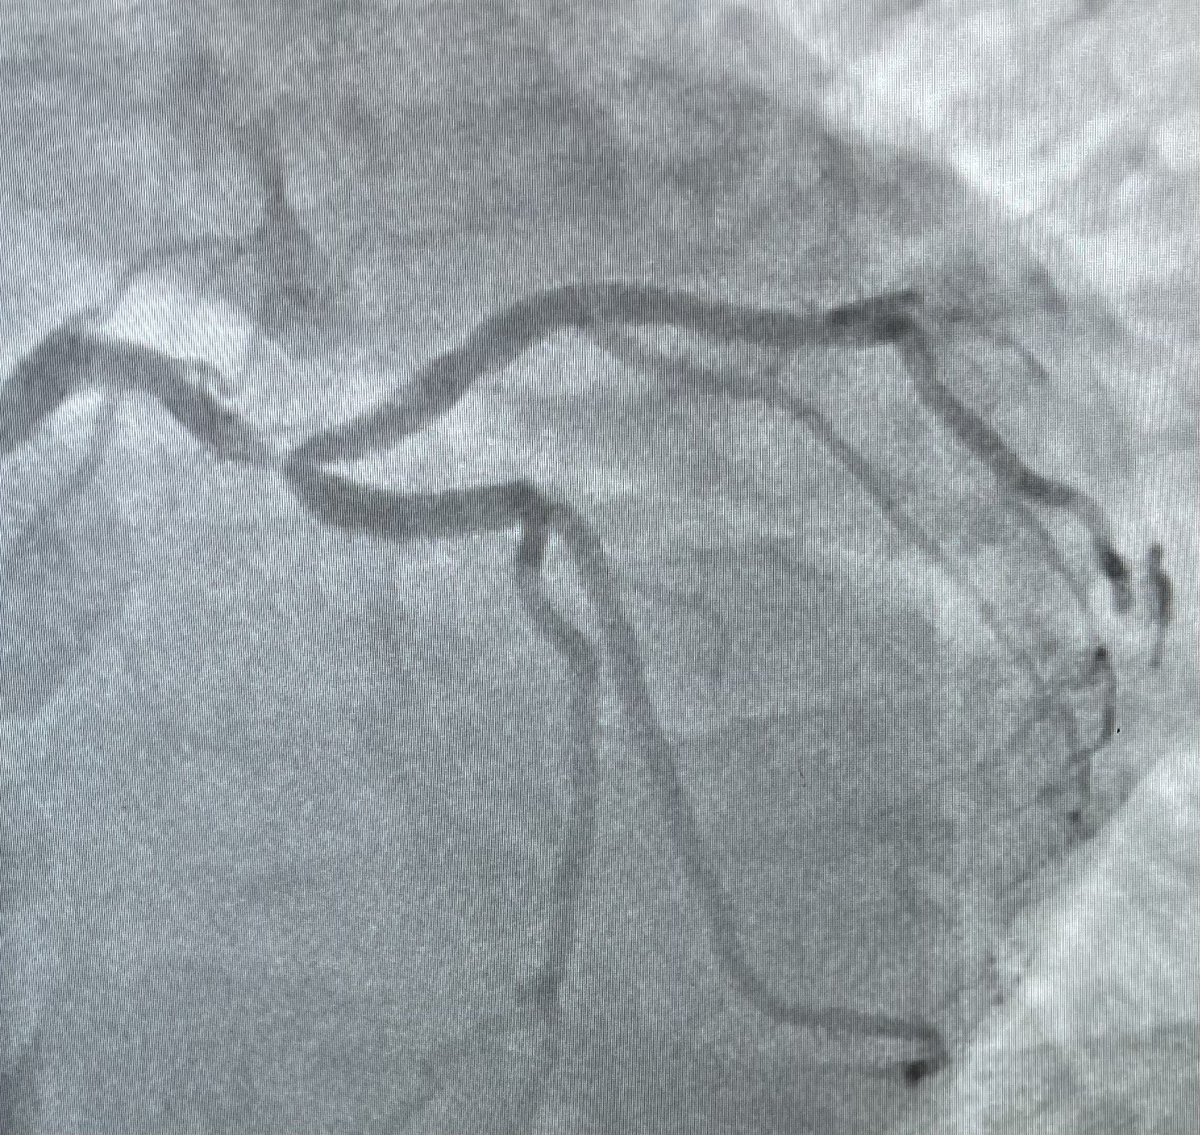

Stent strategy here ? @ShariqShamimMD @aspergian1 @olcayaksoymd @gtheodosmd @evandrofilhobr @AlpeshShahMD @HMHCardioFellow @SVRaoMD @djc795

47 years old male, anterior STEMI? What is your strategy? Direct stenting? @DrRajeshG1 @ShariqShamimMD @ANazmiCalik @MarcoJe80135689 @evandrofilhobr @aspergian1 @jedicath @PCRonline @mmamas1973 #RadialFirst